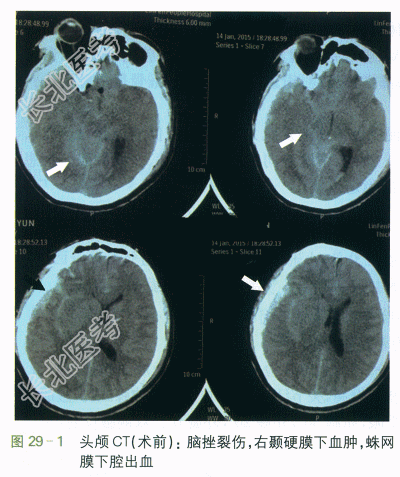

(2)影像学检查:①术前头颅CT示脑挫裂伤,右颞硬膜下血肿,左颞硬膜外血肿,左侧颞骨骨折,颅内积气,蛛网膜下腔出血,鼻窦炎,如图29-1所示。②术后头颅CT示右颞硬膜外血肿去骨瓣术后表现,脑挫裂伤,左筛窦及双蝶窦炎症,左侧颞骨骨折,如图29-2所示。③左膝关节片示左膝关节腘窝处异位骨化可能,如图29-3所示。④髋关节片示两侧髂前上棘及左侧股骨上段考虑异位骨化,左侧股骨头密度改变(考虑骨质疏松可能),如图29-4所示。